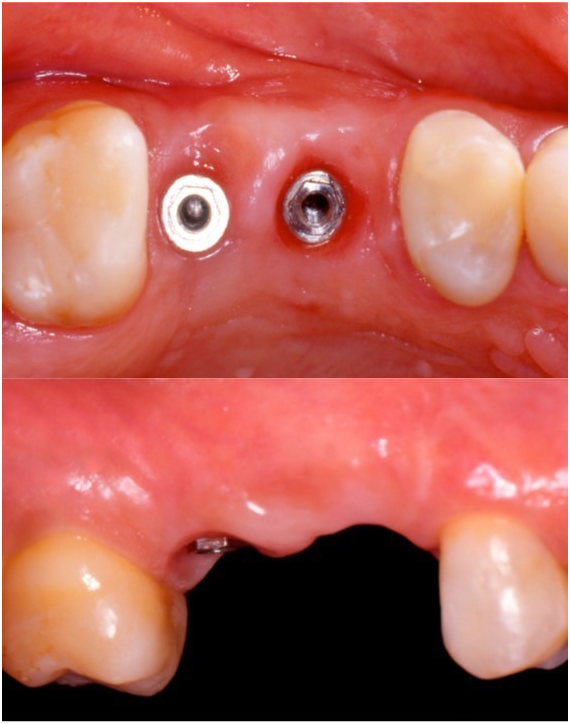

A 45-year-old female patient, after having undergone the installation of dental implants of the external hexagon type in the region of the right upper second premolar and first molar (Figure 1), presented the complaint of depression in the region of the implants, causing an aesthetic defect, visible when smiling (Figure 2). In the anamnesis, no relevant aspects were observed in the patient's previous and current medical history that could interfere in the diagnosis, treatment and prognosis of the intervention to be performed. The correction of the defect was performed after four months of the implants installation, using the technique of mucogingival surgery, in order to gain soft tissue in thickness. Prior to the surgical procedure, the patient received control of biofilm and orientation for maintenance of periodontal health. Then, a subepithelial connective tissue graft (SCTG) was performed using the roller technique. Local infiltrative anesthesia was performed by vestibular and palatine of the defect region using mepivacaine anesthetic 2% with vasoconstrictor. An incision was made with a 15C scalpel blade on the bony crest, further shifted to the palatine, and the dissection plane was crown-apical. Two other slightly divergent incisions were made in the palatal region to divide the epithelial flap. After splitting the flap, an incision at the base of the connective tissue attached to the periosteum was performed (Figure 3) to release the graft, which was moved to the receiving area (vestibular mucosa). The graft was folded under the vestibular flap (Figure 4) and stabilized with isolated suture at the base of the flap. Healing abutments were installed. The vestibular flap was repositioned around the abutments with the graft stabilized by the suture, also performed on the sides and at the base of the wound with interrupted stitches of resorbable Vicryl 5.0 (Figure 5). Compressive suture was performed on the palate over hemostatic sponge of hydrolyzed collagen (Figure 6). The postoperative period consisted of orientations to the patient regarding hygienic care, feeding, rest and prescription of analgesic (paracetamol 750 mg) and anti-inflammatory (nimesulide 100mg). Chemical control of bacterial plaque was also prescribed by means of two 1-minute daily mouthwashes at twelve-hour intervals with 0.12% chlorhexidine digluconate. Patient returned to the postoperative period after seven days, and the suture was removed after 14 days. Patient was kept under control for 30 days, and she was referred for prosthetic rehabilitation after 4 months of surgery. With two months of proservation, tissue gain was observed in thickness (Figure 7). For gingival tissue conditioning, a provisional prosthesis was installed after three months of the mucogingival surgery (Figure 8). It was observed that, after the 6-month period of proservation, the tissue gain in thickness by the SCTG favored the vestibular emergency profile of the prosthesis and the new conformation of the gingival papillae (Figure 9) (Figure 10) (Figure 11).

Figure 2 Tissue depressions in the buccolingual direction in the implants region.